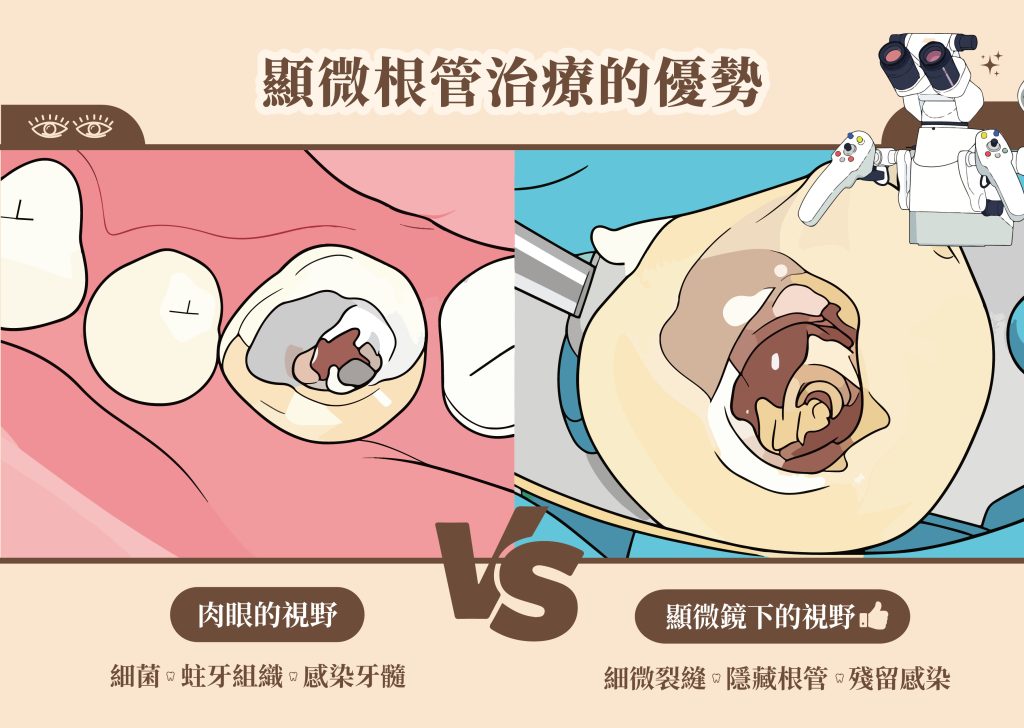

根管治療是處理嚴重蛀牙及牙髓感染的常見療程,目的是透過清除發炎或壞死的牙髓組織,幫助患者最大程度保留健康齒質,延長真牙的使用壽命。而當牙齒內部的根管系統複雜,例如根管彎曲、分岔細小、鈣化阻塞或曾接受過治療但仍反覆感染,且傳統肉眼操作可能很難徹底清潔感染組織時,就需要高倍率手術顯微鏡的幫助,透過「顯微根管治療」提升療程成功率。

在顯微鏡放大與高亮度照明下,醫師會移除壞死牙髓與感染組織,並清潔、擴大與整形根管系統。顯微放大視野有助於辨識細小分岔、彎曲根管或鈣化區域,使處理過程更精細,同時盡量保留健康齒質。